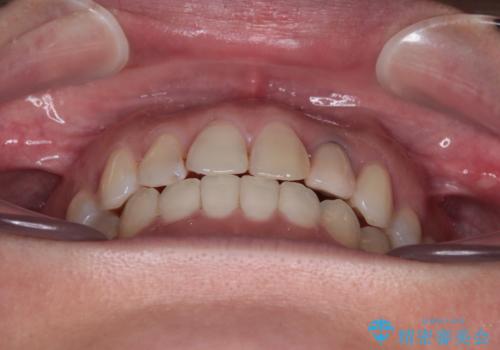

開咬と変色した前歯 インビザライン矯正とオールセラミッククラウン治療

- 前歯の開咬と失活により変色した前歯を気にして来院された患者様です。

開咬の治療は、前歯を閉じるように引っ張り出すよりも、上下臼歯を圧下(骨内にめり込ませる)させることで進める方が長期的に安定した歯列を維持できます。

インビザラインは臼歯の圧下を効果的に行えるため、インビザラインを用いて矯正治療を行うこととしました。

矯正治療が概ね終了した時点で前歯をオールセラミッククラウンにて補綴治療を行い、その後インビザラインにて細かい部分を仕上げていくことしました。